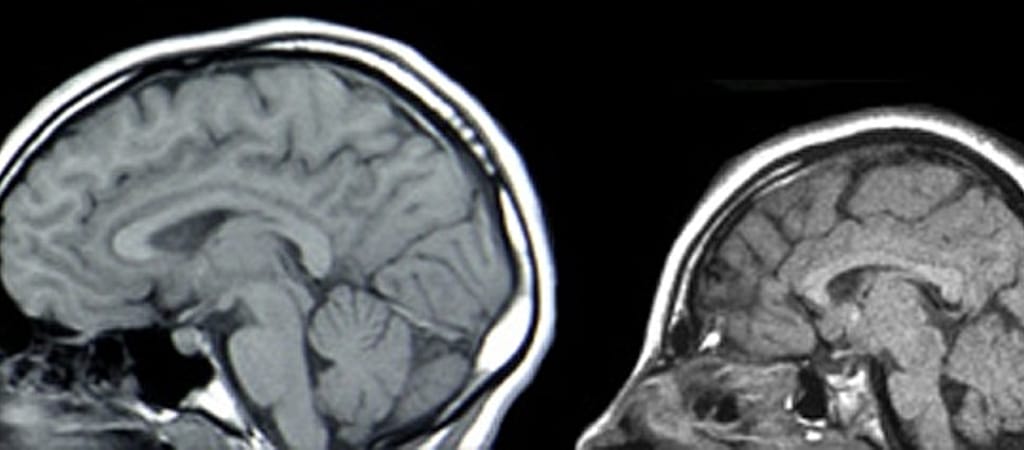

Idén mintegy 1761 csecsemő jött világra kisfejűséggel Brazíliában, amelynek az egészségügyi minisztériuma nemrég az áprilisban megjelent zika-lázzal hozta összefüggésbe a születési rendellenességek megszaporodását - közölte az Egészségügyi Világszervezet (WHO).

A szúnyogok által terjesztett betegség áll a mikrokefáliás, azaz kisfejűség esetek számának drámai megnövekedése mögött - közölte még a hónap elején a brazil egészségügyi minisztérium. A WHO közleménye szerint azonban az összefüggés még megerősítésre vár.

A minisztérium december elején azt mondta, hogy múlt év júliusa óta legalább 739 gyermek - az éves átlag mintegy ötszöröse - jött világra súlyos agyi és koponyaelváltozással az országban. Pár napra rá 1761-re módosította a gyanús esetek számát.

A WHO közleménye szerint december 5-ig az ország 422 városában regisztrált mikrokefália-gyanús gyermekből 19 halt meg.